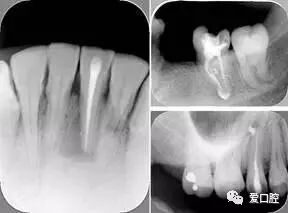

6. 钙化

常见有修复性钙化和增龄性钙化。下面为根管钙化 X 线片。

牙胶尖什么颜色根管治疗的标准步骤以及治疗细节的把握_https://www.jmylbn.com_新闻资讯_第29张

7. 器械折断

右图及下图为器械折断的 X 线片。箭头处示折断器械

牙胶尖什么颜色根管治疗的标准步骤以及治疗细节的把握_https://www.jmylbn.com_新闻资讯_第30张

解决方法: ( 1 )取出。( 2 )通过。( 3 )重新确定工作长度,充填。( 4 )根尖手术。

器械折断可以不用取出,取出的原因多是患者心理因素。留在里面的器械关键是进行消毒,预防性使用抗感染药物,预防感染。